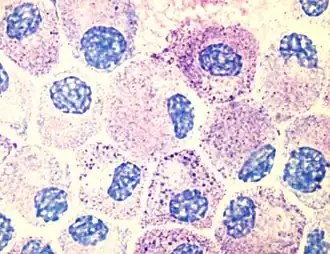

Znajduje zastosowanie jako barwnik w biologii, zwłaszcza jako barwnik histologiczny. Jest barwnikiem polichromatycznym, tzn. barwi ortochromatycznie w tej samej lub zbliżonej barwie niektóre struktury, a inne – metachromatycznie w barwie wyraźnie odmiennej (np. składniki cytoplazmy komórek tucznych dają się wybarwiać błękitem toluidynowym metachromatycznie na czerwono-purpurowo, gdy tło barwi się na niebiesko). Niebieski roztwór błękitu toluidynowego stosuje się w badaniach na obecność ligniny, która wiąże się z włóknami celulozowymi i wzmacnia oraz utwardza ściany komórkowe w roślinach – wynik jest pozytywny przy zmianie zabarwienia z niebieskiego na różowy. Błękit toluidynowy uwidacznia struktury komórkowe przy barwieniu osadu moczu oraz mastocytów w wycinkach skóry, ze względu na obecność heparyny w zasadochłonnych ziarnach w cytoplazmie[a][5].

Przykład barwienia komórek tucznych błękitem toluidynowym. Komórki mogą wydawać się nieco zdegranulowane, ponieważ w czasie doświadczenia były aktywowane antygenem